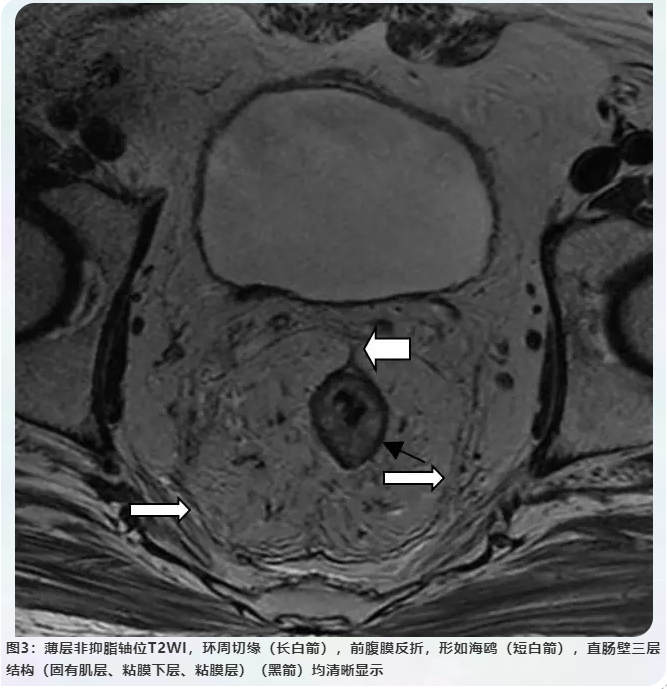

壹生资讯 结直肠癌规范化诊疗 影像篇 Mri精准诊断和评估直肠癌

壹生资讯 结直肠癌规范化诊疗 影像篇 Mri精准诊断和评估直肠癌